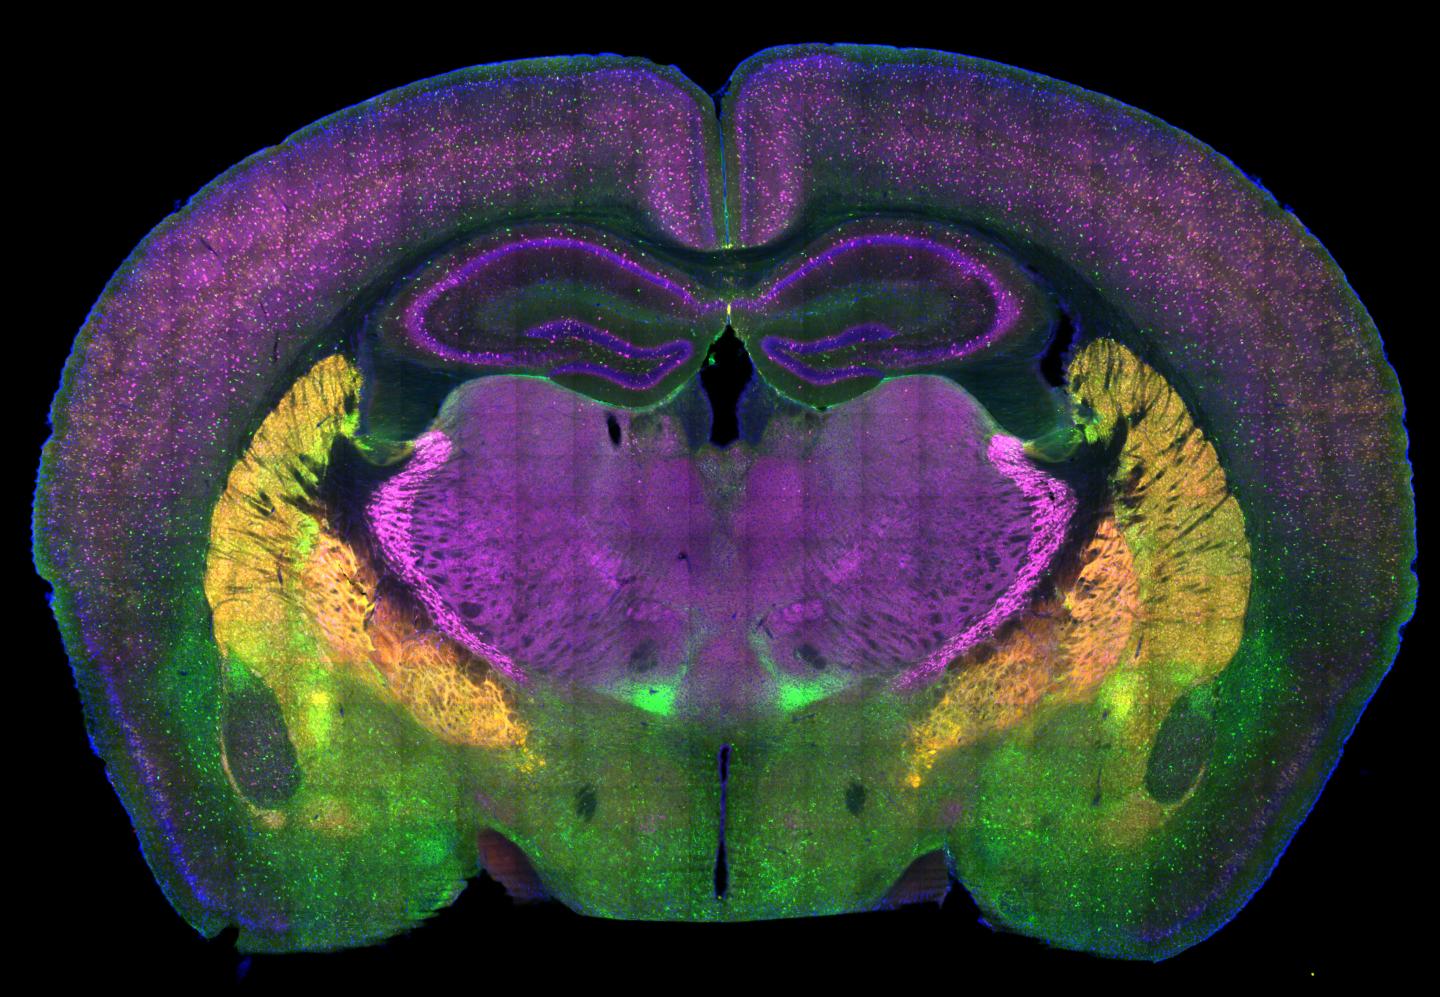

image: A cross-section of a mouse brain reveals some of the regions involved in the choice between social approach and avoidance.

Damon Page lab @ScrippsResearch

The study, from the lab of neuroscientist Damon Page, PhD, uses a variety of innovative techniques to address this challenge, finding two specific circuits capable of independently controlling social preference in mice. Both link the areas of higher-level thought and decision-making in the prefrontal cortex to the emotional regulation center of the brain, the amygdala.

The group found that one neural circuit connecting the mouse infralimbic cortex to the basolateral amygdala impairs social behavior if its activity is dialed down. The other key circuit connects the prelimbic cortex to the basolateral amygdala. Dialing up activity of that circuit produced similarly impaired social behavior, says Aya Zucca, the study's co-first author.